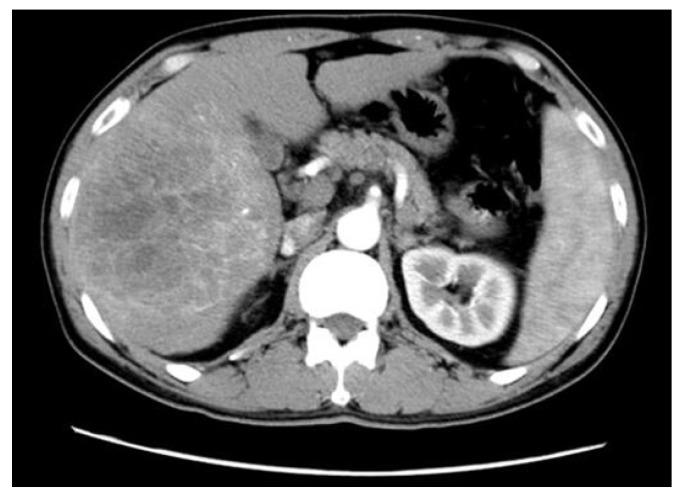

There is no information regarding transarterial chemoembolization (TACE) as a postoperative management after hepatic resection for patients with hepatitis B virus (HBV)-associated intrahepatic cholangiocarcinoma (ICC). Forty-two patients with pathological confirmation of HBV-associated ICC were enrolled. Prognostic impact of the clinicopathological factors as well as postoperative TACE were evaluated. Computed tomography findings of HBV-associated ICC were assessed. Tumor size of larger than 5 cm (hazard ratio [HR], 5.654; 95% confidence interval [CI], 1.175 to 27.204; P = 0.031), postoperative TACE (HR, 0.123; 95% CI, 0.023 to 0.643; P = 0.013), and lymph node metastasis (HR, 3.284; 95% CI, 1.236 to 8.724; P = 0.017) revealed to be independently associated with survival outcomes of patients with HBV-associated ICC. Application of TACE, as a postoperative management to control early local recurrence on the basis of hepatic arterial phase enhancement, significantly prolonged survival outcomes (1-yr, 88.9%; 3-yr, 77.8%; 5-yr, 66.7%), compared to the patients who did not receive TACE (1-yr, 63.6%; 3-yr, 30.8%; 5-yr, 13.0%). When analyzed according to the status of hepatic arterial phase, arterial phase enhancement demonstrated a favorable trend on prognosis of patients with HBV-associated ICC without statistical significance (HR, 0.435; 95% CI, 0.140 to 1.359; P = 0.141), and TACE independently improved overall survival of patients with arterial phase enhancement (HR, 0.105; 95% CI, 0.014 to 0.774; P = 0.027). Put together, our results indicate that postoperative TACE effectively improves prognosis of HBV-associated ICC with arterial phase enhancement in CT scans. Large-sized trials are required for our results to be applied in clinical medicine.

目前尚无关于经肝动脉化疗栓塞术(TACE)作为乙型肝炎病毒(HBV)相关肝内胆管细胞癌(ICC)患者肝切除术后管理的信息。本研究共纳入 42 例经病理证实的 HBV 相关 ICC 患者。评估了临床病理因素以及术后 TACE 的预后影响。评估了 HBV 相关 ICC 的 CT 表现。肿瘤直径大于 5cm(风险比[HR],5.654;95%置信区间[CI],1.175 至 27.204;P=0.031)、术后 TACE(HR,0.123;95%CI,0.023 至 0.643;P=0.013)和淋巴结转移(HR,3.284;95%CI,1.236 至 8.724;P=0.017)是与 HBV 相关 ICC 患者生存结果独立相关的因素。基于肝动脉期增强,TACE 作为一种术后管理方法,用于控制早期局部复发,与未接受 TACE 的患者相比,显著延长了生存结果(1 年,88.9%;3 年,77.8%;5 年,66.7%)(1 年,63.6%;3 年,30.8%;5 年,13.0%)。根据肝动脉期的状态进行分析时,动脉期增强显示出对 HBV 相关 ICC 患者预后的有利趋势,但无统计学意义(HR,0.435;95%CI,0.140 至 1.359;P=0.141),TACE 独立改善了动脉期增强患者的总生存(HR,0.105;95%CI,0.014 至 0.774;P=0.027)。综上所述,我们的研究结果表明,术后 TACE 可有效改善 CT 扫描显示动脉期增强的 HBV 相关 ICC 的预后。需要进行大型临床试验,以便将我们的研究结果应用于临床医学。